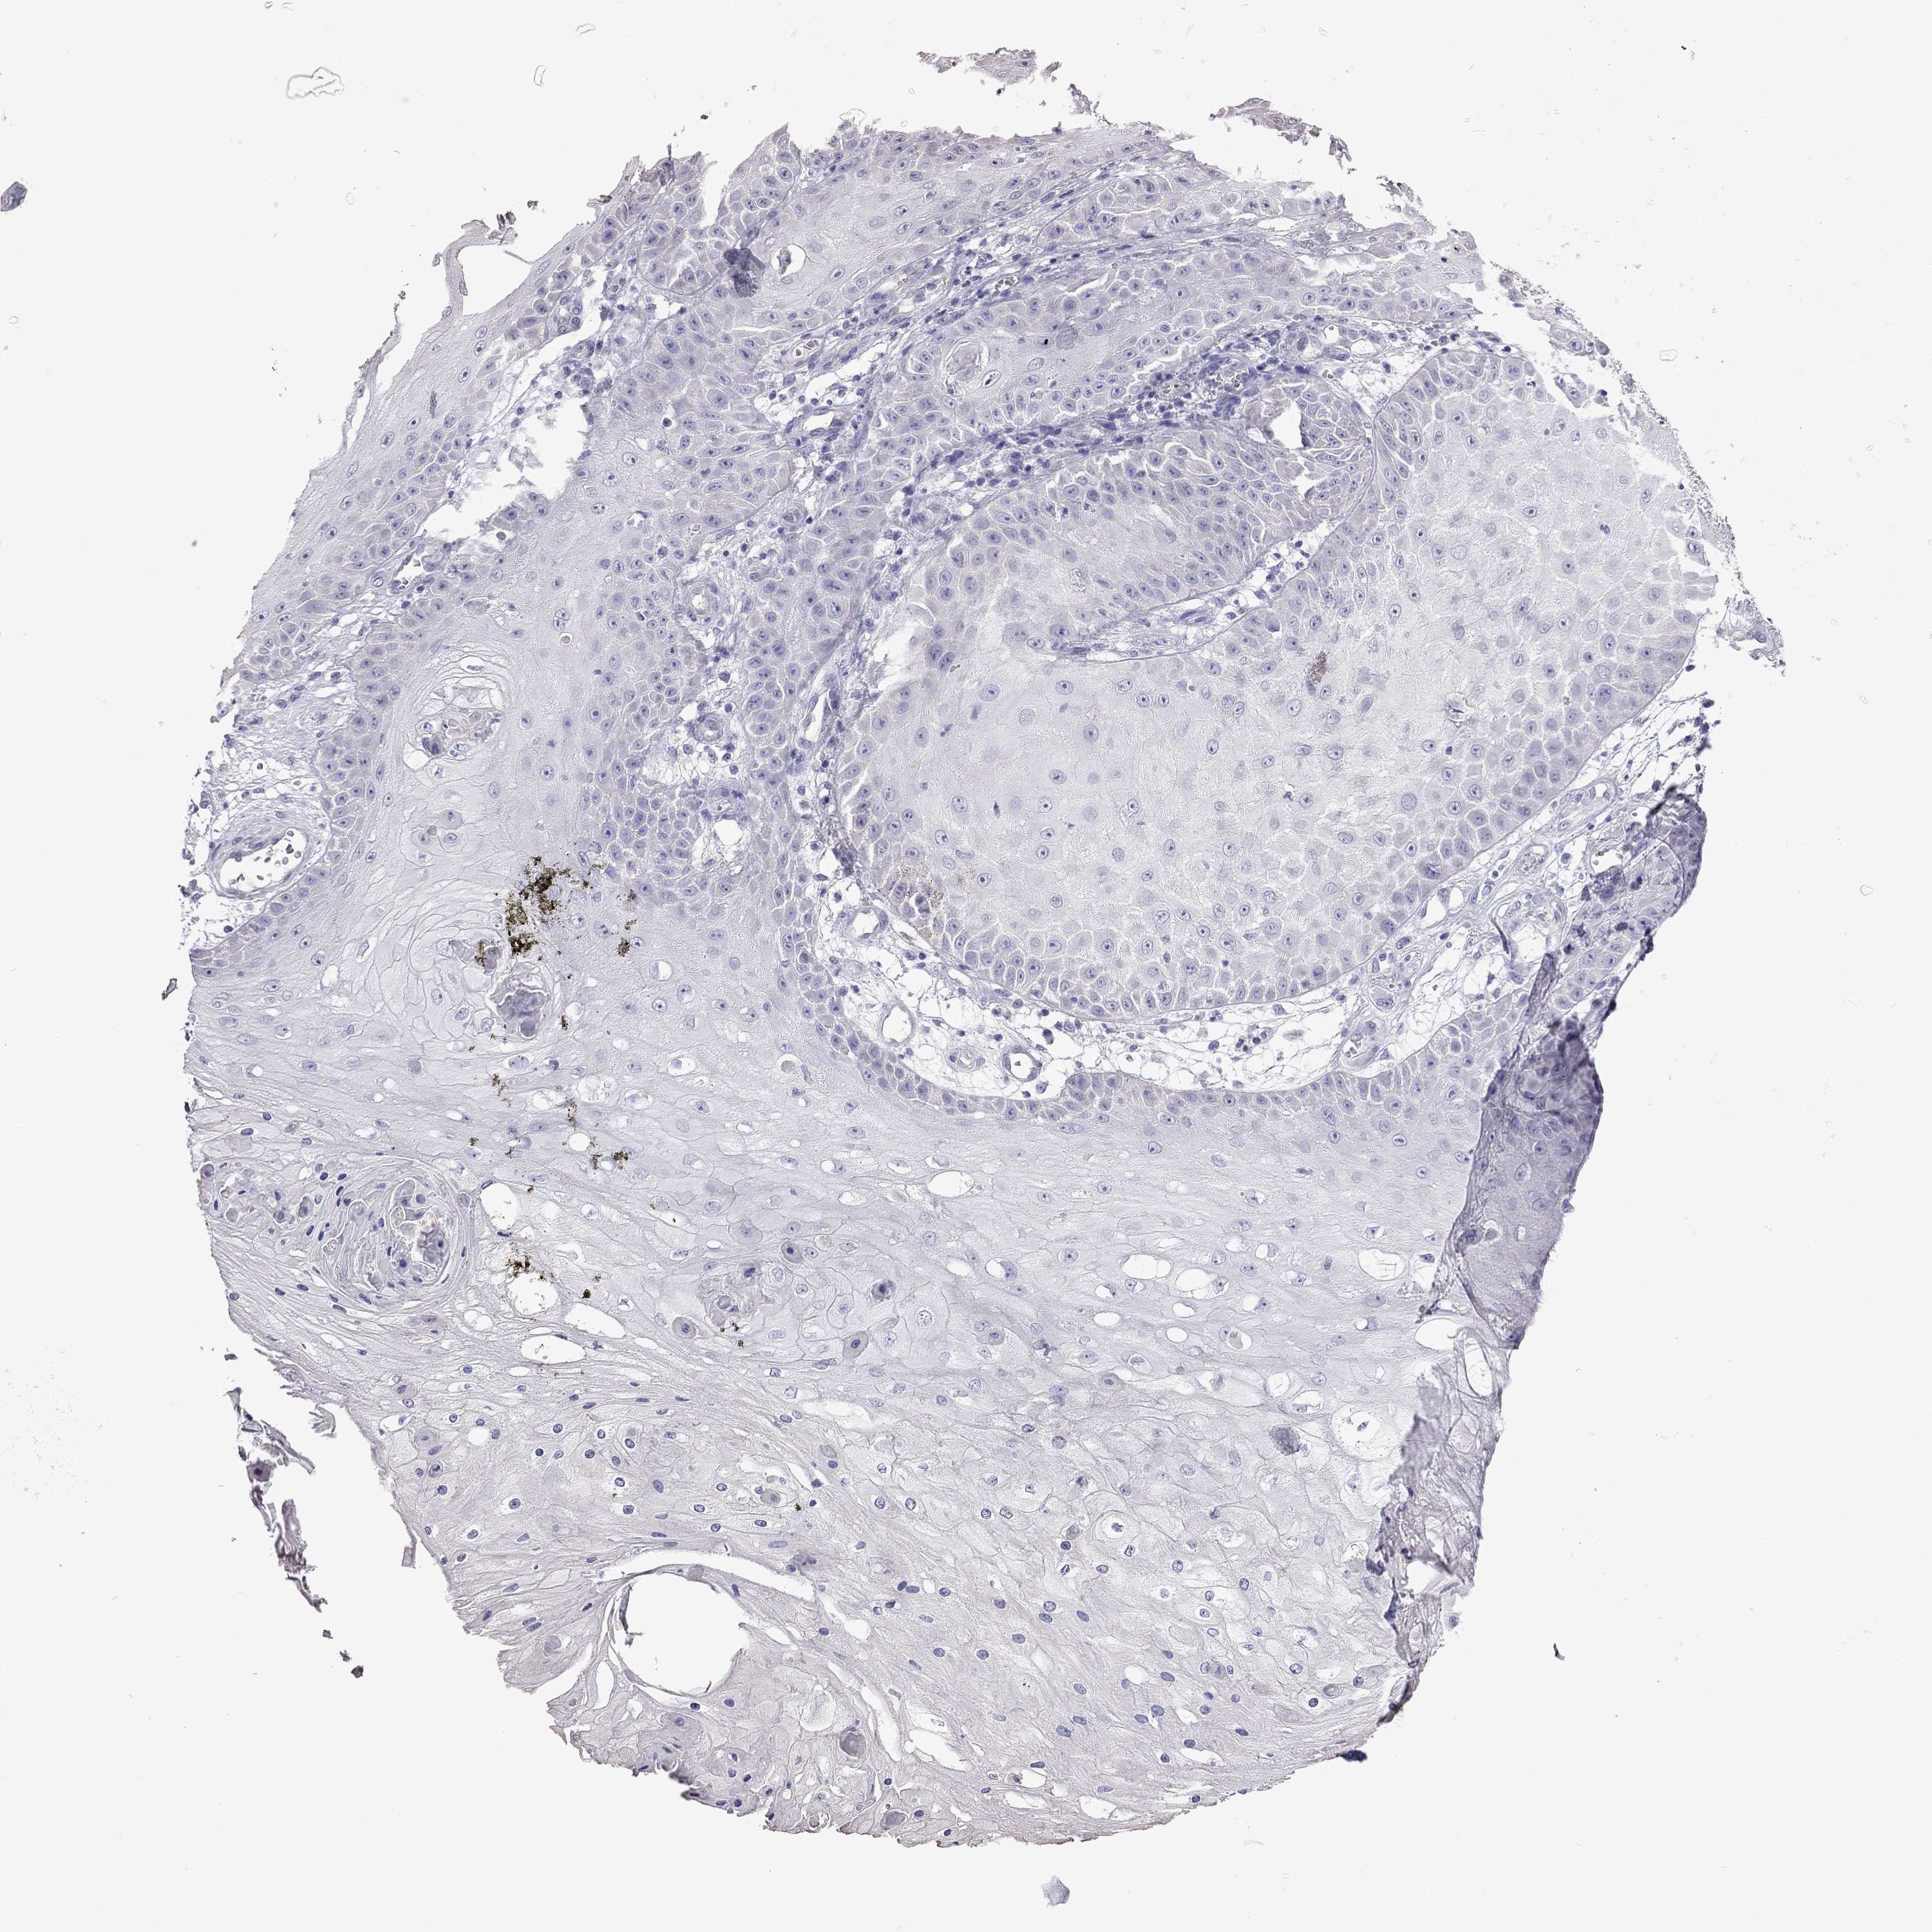

CANCER SKIN CANCER Show tissue menu

Basal cell and squamous cell cancer

SKIN CANCER - Protein expressioni

A mouse-over function shows sample information and annotation data. Click on an image to view it in a full screen mode. Samples can be filtered based on level of antibody staining by selecting one or several of the following categories: high, medium, low and not detected. The assay and annotation is described here.

Each image is clickable and will lead to virtual microscopy that enables deeper exploration of all samples and also displays staining intensity scores, fraction scores and subcellular localization as well as patient and tissue information for each sample.

Antibody HPA076844

Basal cell carcinoma

Squamous cell carcinoma, NOS